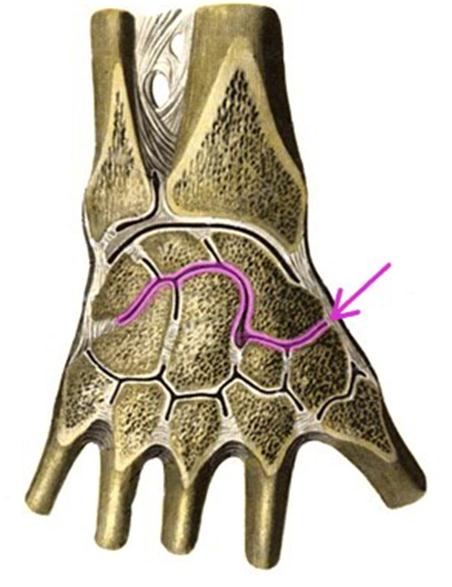

S: Стрелка указывает на art....

-:carpometacarpea

-:radiocarpea

+:mediacarpea

-:carpometocarpea policis

-:intercarpea